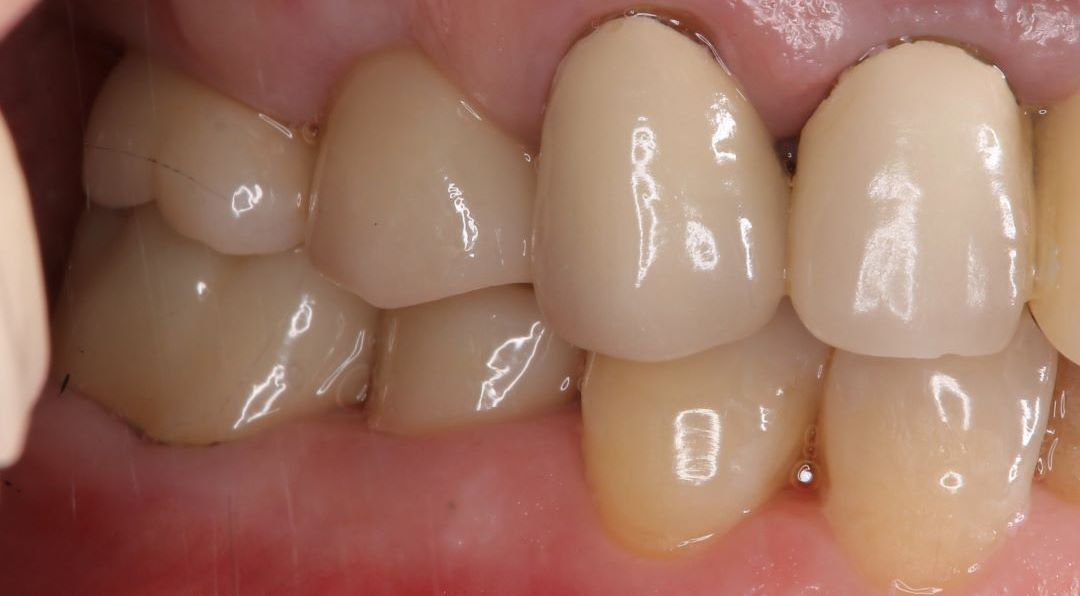

case 01.

BEFORE

AFTER

健康な歯を削ることに抵抗があり、より歯を長く保たせる治療を希望し来院された。

(リスク)